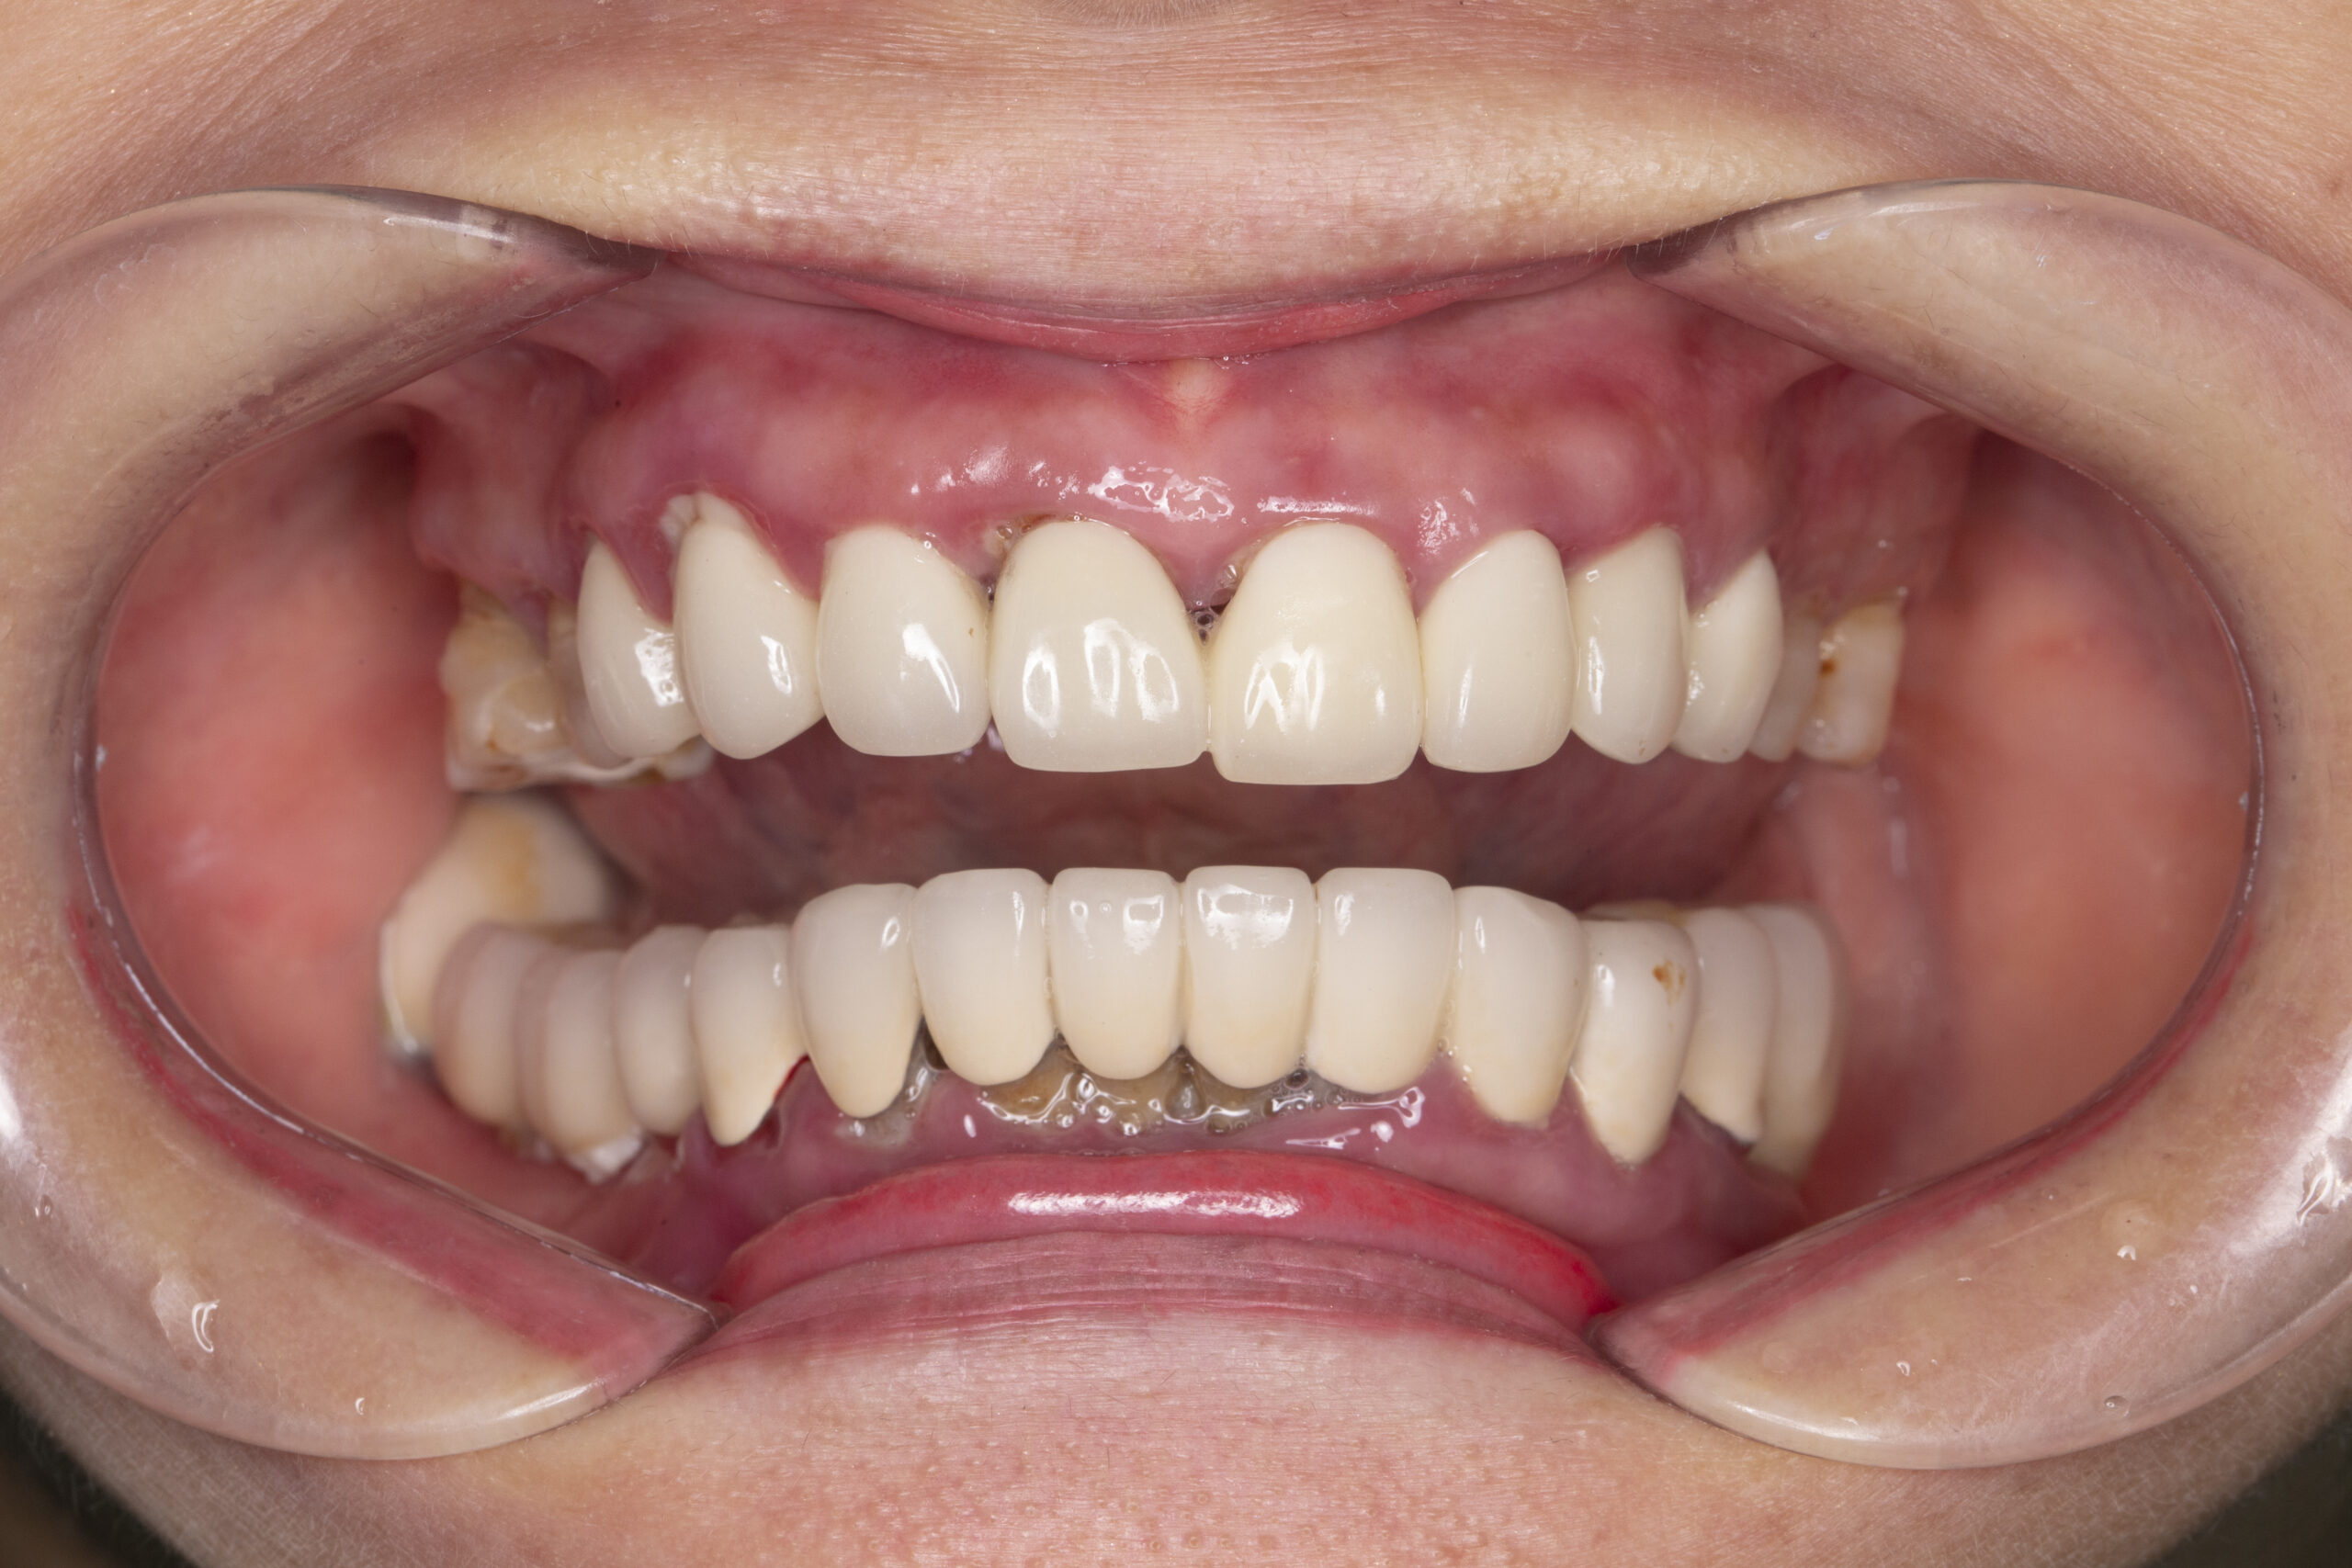

Trường hợp mất răng của cô Nguyễn Kim Hoa (64 tuổi; Hoàn Kiếm- Hà Nội); Trồng Implant toàn hàm dưới

Kế hoạch điều trị:

+ Chia thành 2 đợt điều trị cấy toàn hàm dưới trước

+ Trồng răng toàn hàm dưới 6 trụ Neodent của Thụy Sỹ: 22,5 Triệu x 6 = 135 Triệu

+ Làm hàm sứ rời Zirconia 12 răng: 54 Triệu

Tổng chi phí điều trị trồng răng toàn hàm trên: 135 Triệu + 54 triệu = 189 Triệu